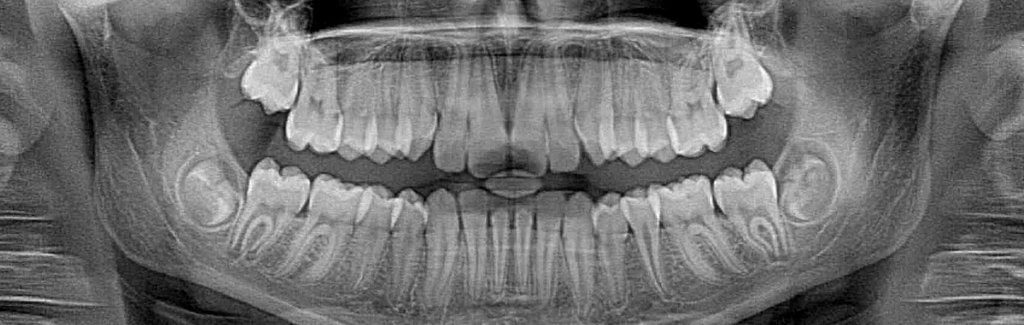

Dental x-rays enable dentists to see decay inside teeth that would not be visible to the naked eye. This allows us to act earlier against cavities, which is much better for the teeth. However, x-rays do expose patients to radiation, which is why you always wear a lead apron when the images are being taken. Thanks to advances in technology, there is now a safer way to take these images.

Film x-rays have been used in dentistry for decades. In the past few years, many forward-thinking dentists like Dr. Hammond have invested in digital x-ray technology. Film x-rays cost a bit less than digital x-rays but the increased exposure to film x-rays is more harmful to a patient’s overall health. Our digital x-ray emits as much as 85 percent less radiation than traditional x-ray technology.

Digital x-rays are one of the most important new advances in our office. We are not only able to reduce your exposure to radiation but also increase the diagnostic proficiency. In addition to increased diagnostics, we reduce the amount of harmful chemicals and other waste materials associated with traditional x-ray technology. The reduction in waste was a big consideration when deciding to invest in digital technology. We pride ourselves in being environmentally responsible.